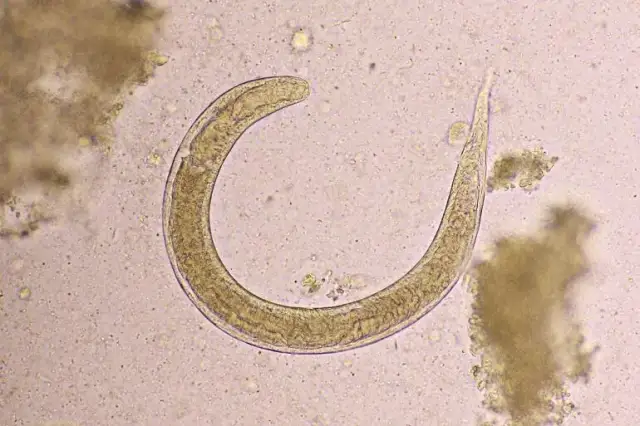

Czy leki na owsiki są na receptę? Sprawdź, jakie leki są dostępne bez recepty i jak skutecznie leczyć owsicę u dzieci i kobiet w ciąży.